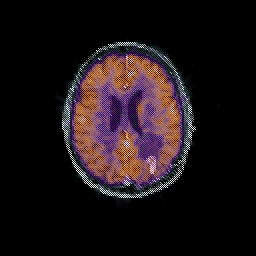

Glioma overlay -- Slice #74

[Home][Help][Clinical] Slice 74